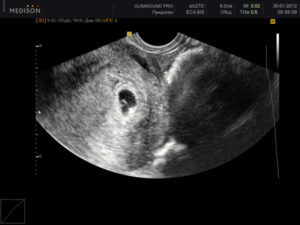

Узи на 5 неделе беременности

УЗИ на пятой неделе беременности покажет: размеры матки, количество плодных яиц и место, где локализуется плод в матке.

Уже на пятой неделе начинает работать сердечно — сосудистая система, поэтому грамотный специалист в ходе ультразвукового исследования, путем сопоставления сердечного ритма и двигательной активности плода, сможет оценить и спрогнозировать его жизнедеятельность.

Врачи не рекомендуют делать УЗИ на 5 неделе беременности, так как срок еще слишком мал, чтобы исследование было достаточно информативным. Если же вы одна из тех нетерпеливых будущих мам, которые уже записались на УЗИ на 5 неделе, то вы можете узнать следующие новости:

- Где расположено плодное яйцо. В норме плодное яйцо на 5 неделе беременности расположено в полости матки. Если врач обнаруживает плодное яйцо вне матки (в маточной трубе или в другом месте), то говорят о внематочной беременности.

- Если у вас двойня, то уже на 5 неделе беременности УЗИ скорее всего сможет это показать.

- Размеры плодного яйца: по этому показателю врач уточняет срок беременности. Размеры плодного яйца на 5 неделе могут варьировать от 6 мм до 18 мм.

- Есть ли сердцебиение. В норме сердце эмбриона начинает биться на 5 неделе беременности, однако не все аппараты УЗИ способны зарегистрировать сердечную активность на этом сроке. Вагинальное УЗИ в этом случае более чувствительно и чаще выявляет сердцебиение на 5 неделе. Не расстраивайтесь, если УЗИ на 5 неделе не показало сердцебиения – это еще не говорит о замершей беременности. Вам необходимо пройти УЗИ повторно через 1-2 недели.

УЗИ

Если будет назначено УЗИ на 5 неделе беременности, то исследование позволит определить место прикрепления эмбриона в матке, а к концу недели можно будет разглядеть и сердцебиение.

Совет! Если срок беременности перевалил за 5 недель и при проведении УЗИ сердцебиение не было выявлено, то это не означает, что развитие малыша идет неправильно. Скорее проблема в возможностях оборудования для проведения исследования.